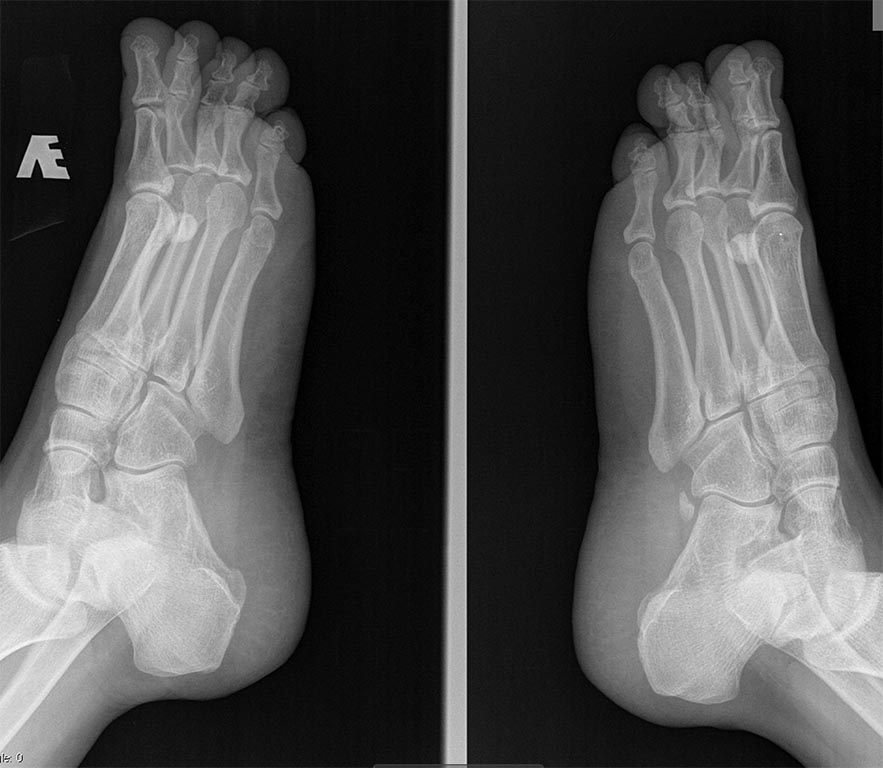

По рентгенограмме нарушена парабола Лельевра, длинная 4 ПК. Думаю стоит выполнить укорачивающую Вейл остеотомию под контролем ЭОП для нормализации данной параболы. Клинически, если длина 4 пальца восстановилась, то можно ограничиться Вейлем, если нет, то выполнить укорачивающую остеотомию основной фаланги 4-го пальца. Я пальцы фиксирую трансартикулярно 1-2-мя спицами. В данном случае надо стараться укоротить 1-м Вейлем, думаю, пациентка требовательна к внешнему виду стопы. Отек и утолщение 4-го пальца будут её беспокоить, появятся (не дай бог) натоптыши

Обычно с подобными проблемами обращаются женщины 20-30 лет. Что заставило пациентку решиться на такой шаг именно сейчас? Раньше денег не было? Времени? Ведь грубой разницы в длине пальцев нет. И уж никак такие пальцы не помешают подбору обуви. Засада сидит глубоко в голове таких пациенток. Очень желательно попробовать разобраться в ней до операции. Ситуация то, в принципе, патовая. Можно укоротить плюсневую кость и получить переходную метатарзалгию. Сейчас нет боли и натоптышей, а тут появятся. Да еще шрам после операции. Лучше укоротить основную фалангу. Еще лучше сделать это чрескожно. В этом случае хоть шрама не останется. Но палец станет толще. И относительно, поскольку при той же толщине станет короче и будет восприниматься более толстым. А он и так заметно толще третьего. И абсолютно, поскольку мягкие ткани присборятся. Плюс какая-никакая костная мозоль. Так что вероятность получения негативного косметического или функционального результата, а значит и недовольного пациента, очень велика. О таких возможных результатах нужно обязательно поставить в известность пациентку. И все-таки, постараться разобраться в причинах ее желания сделать операцию. У меня была молодая пациентка, которой отец в 12 лет сказал, что у нее некрасивые стопы. С тех пор она ненавидела их. И операция, которую я ей сделал, принесла только разочарование. Хотя поставленные задачи были выполнены. Сейчас Вашей пациентке кажется, что причина ее недовольства - длина 4-х пальцев. А потом начнет казаться, что толщина. А фиксировать пальцы можно по-всякому: спицей, повязкой, пластырем. В зависимости от способа операции, размеров операционной раны, Ваших навыков.

А по теме. Мне кажется параболу не стоит трогать - нет болей нет хирурги , ток фалангу укоротить!

А какой диагноз ставят пациенту, который хочет изменить форму нормального носа или увеличить нормальные молочные железы? Возможный диагноз в данном случае "нарушение взаимоотношений длин пальцев стоп". В МКБ такого конечно нет. Но косметические операции выполняются во всем мире и давно доказали право на существование. Главное сделать операцию правильно и не навредить. А шкала AOFAS к оценке подобных состояний отношения не имеет. Хотя, в ней есть пункт про обувь. Если пациент не может носить модную обувь, а вынужден покупать просто удобную, снимается 5 баллов.

Конечно то, что я написал - не диагноз. Я и сказал, что в МКБ такого не найдешь. Но и болезни никакой нет. Случай, который Вы продемонстрировали, интересный. Было бы еще интереснее увидеть эту стопу до операции. Чтобы понять, насколько толще стал оперированный палец в финале. А вот сходства Вашего случая с обсуждаемым я не увидел. В предложенном на форум случае третий палец явно тоньше соседних и пятого. Скорее можно говорить о гипоплазии третьего пальца. Хотя, какая разница? Жалоба больной понятна. Как устранить слегка избыточную длину 4-го пальца тоже, вроде, понятно. Вы же не советуете сделать такую же операцию, как в Вашем примере? Если же говорить о похожем случае, то и я предлагаю посмотреть на нечто подобное.

К вопросу параболе Лельевра, как вы думаете к чему приведет её восстановление. Остеотомия Вейля 3 и 4 лучей, так сказать попробовать помочь природе.